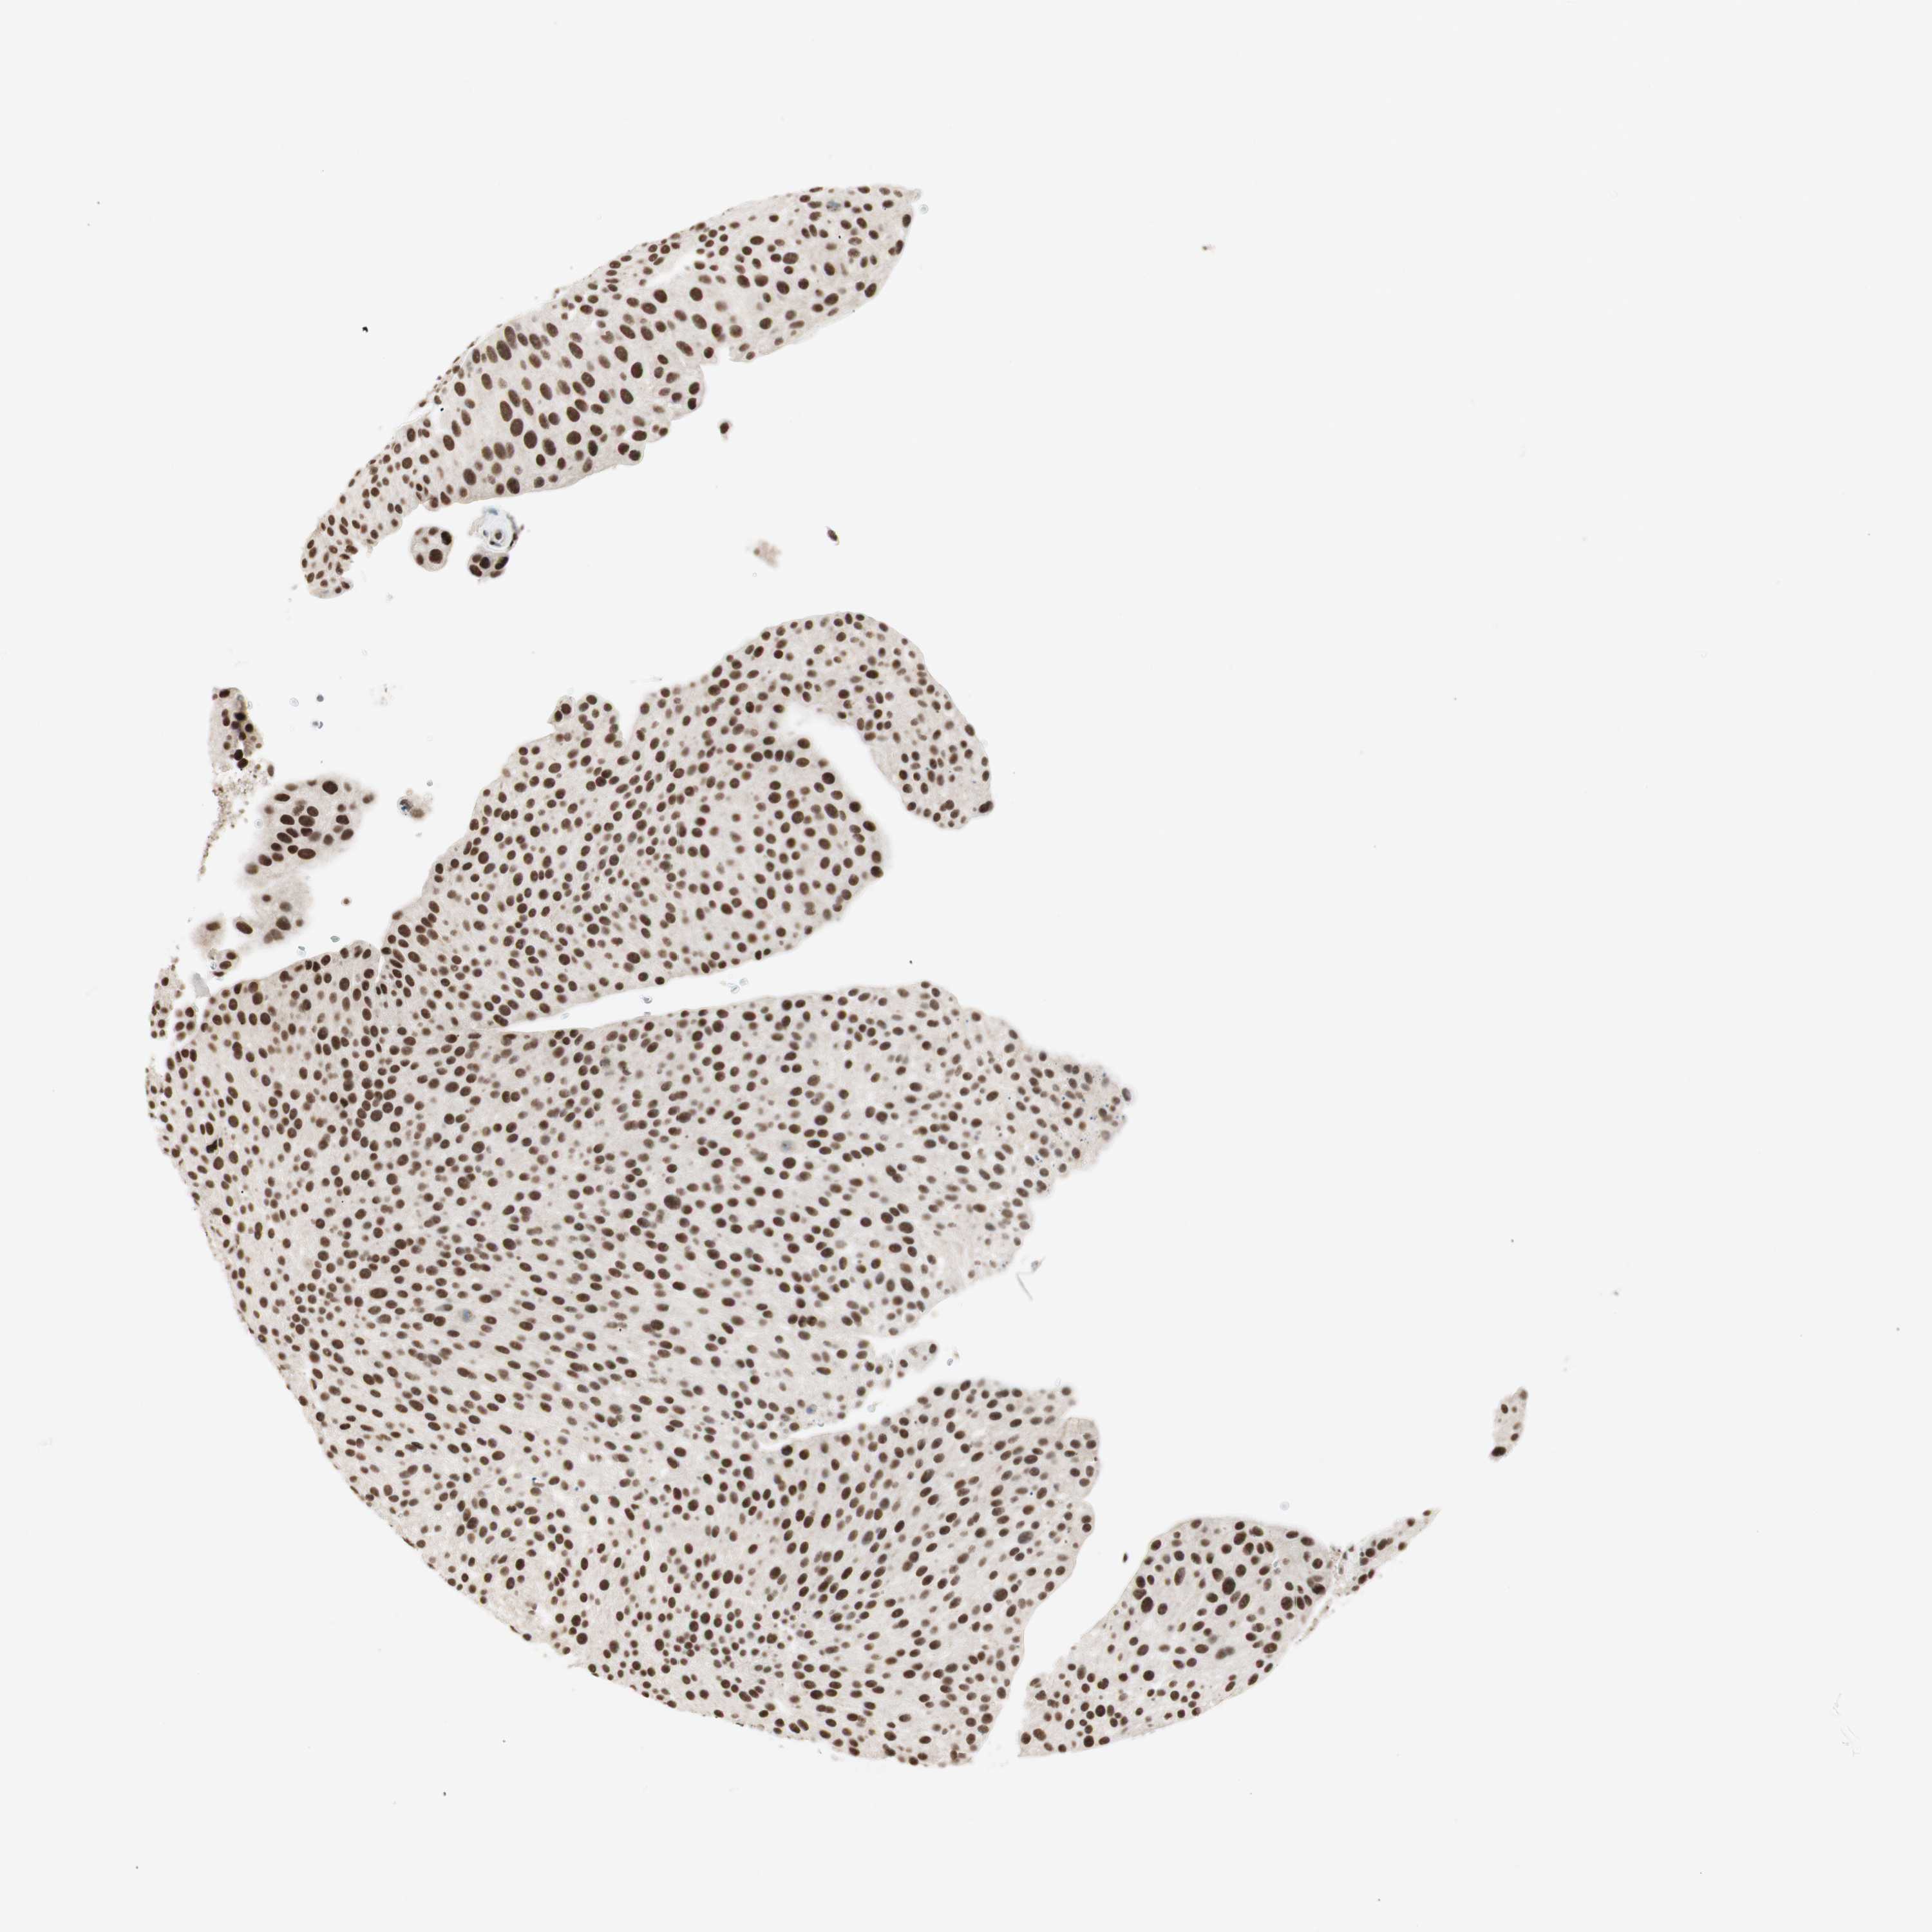

UROTHELIAL CANCER - Protein expressioni

A mouse-over function shows sample information and annotation data. Click on an image to view it in a full screen mode. Samples can be filtered based on level of antibody staining by selecting one or several of the following categories: high, medium, low and not detected. The assay and annotation is described here.

Antibody stainingi

Antibody staining in the annotated cell types in the current human tissue is reported as not detected, low, medium, or high, based on conventional immunohistochemistry profiling in selected tissues. This score is based on the combination of the staining intensity and fraction of stained cells.

Each image is clickable and will lead to virtual microscopy that enables deeper exploration of all samples and also displays staining intensity scores, fraction scores and subcellular localization as well as patient and tissue information for each sample.

Antibody HPA003916

Antibody CAB037318

Staining

High

Medium

Low

Not detected

Intensity

Strong

Moderate

Weak

Negative

Quantity

>75%

75%-25%

<25%

None

Location

Nuclear

Cytoplasmic/membranous

Cytoplasmic/membranous,nuclear

Urothelial carcinoma, Low grade

Urothelial carcinoma, High grade

Urothelial carcinoma, NOS